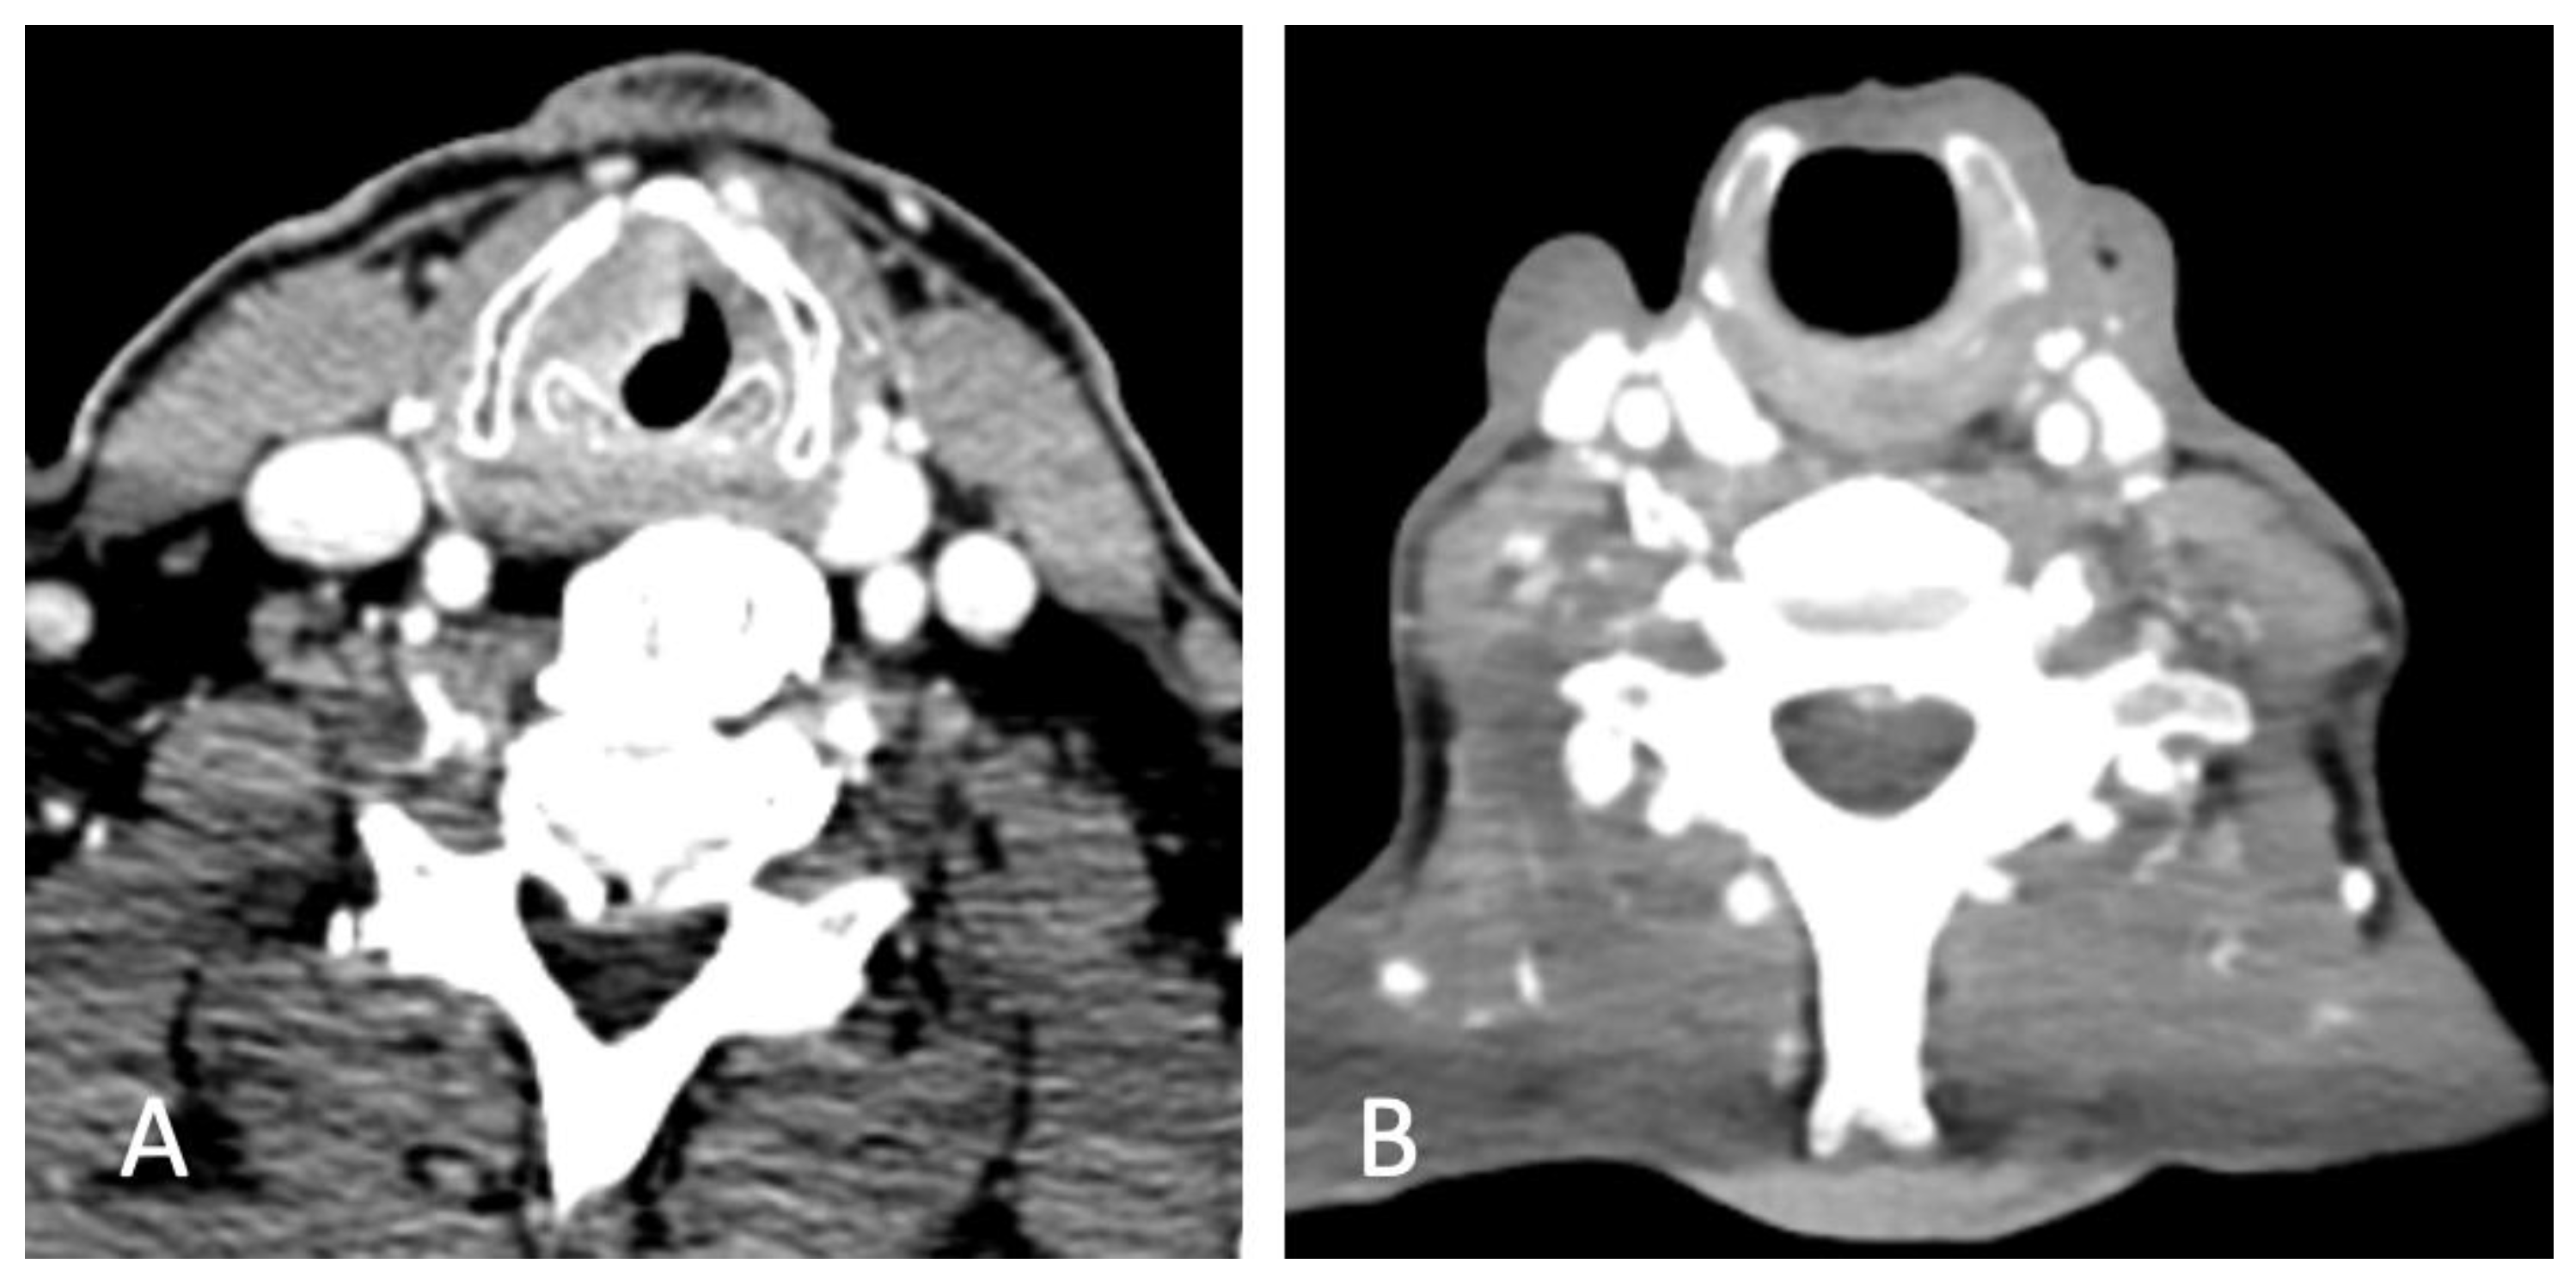

2.2. Surgical Technique